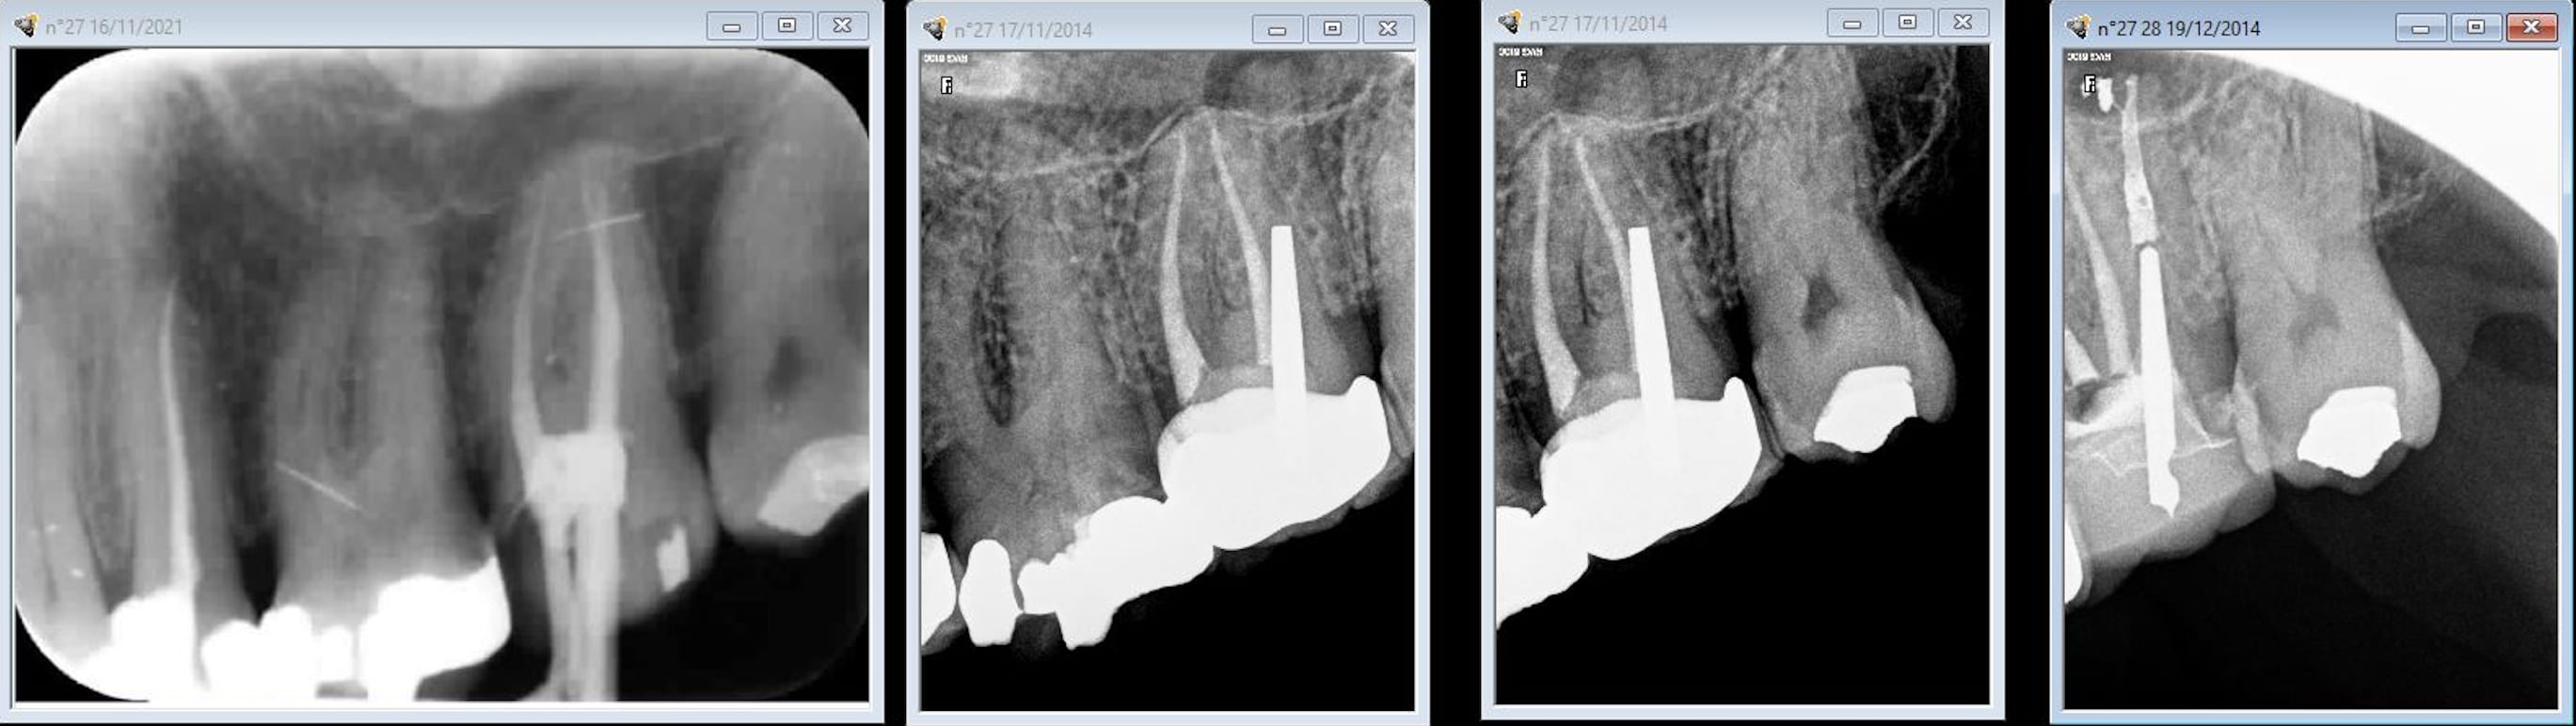

La radio de fin de tt initial est à gauche ( pas se fier aux dates ca a été fait vers 2007 et le RTE en 2014) Ca avait l'air pas mal même si le mV2 a été oublié le souci c'est que le cone dans le palatin a disparu sous l'inlay core. Ca a été repris par un ommi sous digue et micro.

en mesial de la 27 y a une carie...